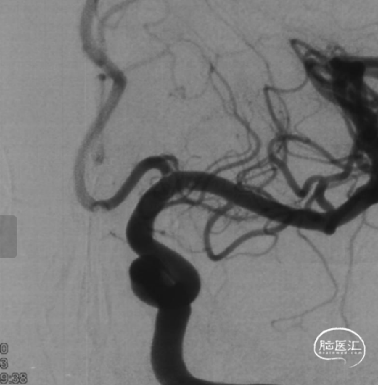

TB Plus 4/35

3、释放TB Plus过程中,头端铆钉效果满意,释放过程顺滑。

4、通过微导丝按摩,可以使TB Plus贴壁效果更加。

5、FD植入后,动脉瘤明显造影剂瘀滞,效果显著。

6、Tubridge Plus材料改进后通体显影,可以更好观察支架的贴壁性及术中打开情况,提高释放安全性。